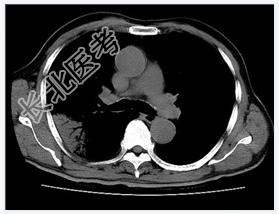

- [材料题] 患者,男性,47岁。发热,咳嗽,右胸痛3天入院。查体.体温,38℃。右上肺呼吸音减低,叩诊实音。心脏无异常。行胸部CT平扫。

- 简答题1、请问该病例诊断是什么?

- 简答题2、请问诊断依据是什么?

- 简答题3、鉴别诊断有哪些?